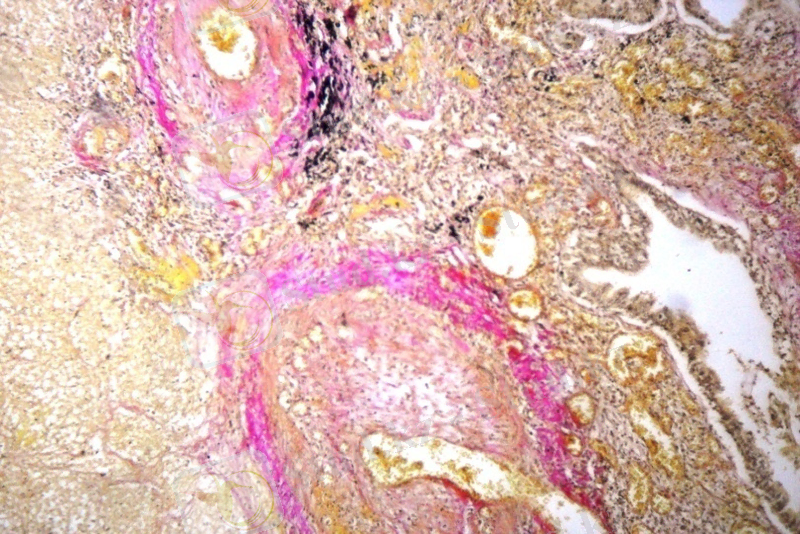

Қан тамырларының айналасындағы фиброзды тіннің өсуінің нәтижесінде саңылаулары тарылып, олардың перикалибровкасы және резервтегі қан тамырларының ашылуынан пайда болған «ангиоматоз» байқалды (7 сурет) . Бұл құбылысты өкпе тінінің деформациясы нәтижесінде дамыған өкпе артериясы жүйесінің гипертензиясымен түсіндіруге болады. Перифокалды қабыну аймағы ошақты серозды пневмония түрінде көрініс беріп, альвеолалардың қуысында жас макрофагалды элементтерден және бірлі жарым фибрин жіпшелерінен тұратын серозды экссудат анықталды (8 сурет) .

7-ші сурет. Қан тамырларының 8-ші сурет. Альвеолалардың қуысында

перикалибровкасы, резервтегі қан жас макрофагтар және фибрин

тамырларының толыққандылығы. жіпшелері. Гематоксилин және эозин.

Ван-Гизон бояуы. Үлкейту х 100. Үлкейту х 200.